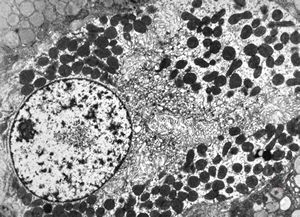

normal mucosa - stomach - parietal cell